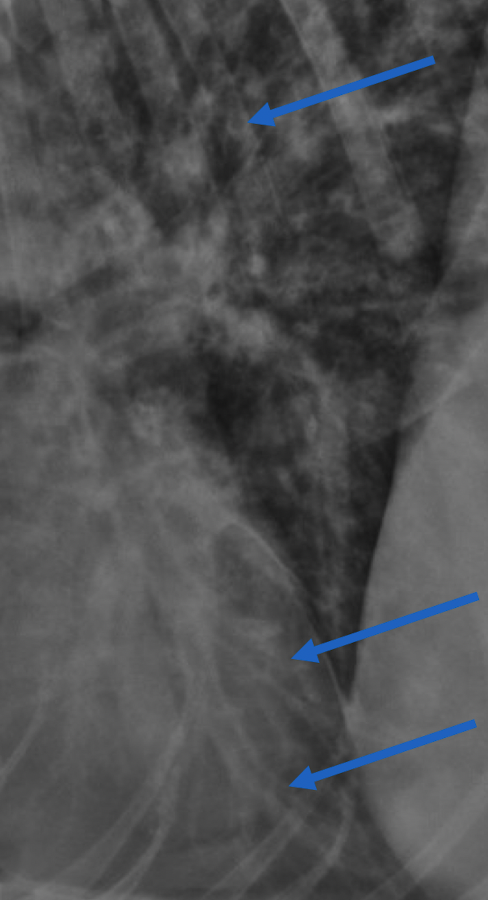

pneumo?

no - just normal deep chested dog- can see vessels in space below heart if you zoom